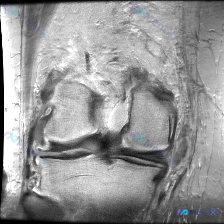

这是一张单张膝关节MRI冠状位影像,分析可见:

- 序列与解剖:为冠状位T2/质子密度加权序列,可显示股骨内外髁、胫骨平台、内外侧半月板及侧副韧带

- 影像学所见:

- 内外侧半月板体部未见明显信号异常、形态正常

- 股骨内外髁关节软骨面轮廓尚可,胫骨平台关节面无明显骨质缺损变形

- 股骨胫骨骨髓未见明显异常高信号(无骨髓水肿)

- 内外侧副韧带无连续性中断或水肿

- 无明显关节腔积液

- 关节间隙无明显狭窄